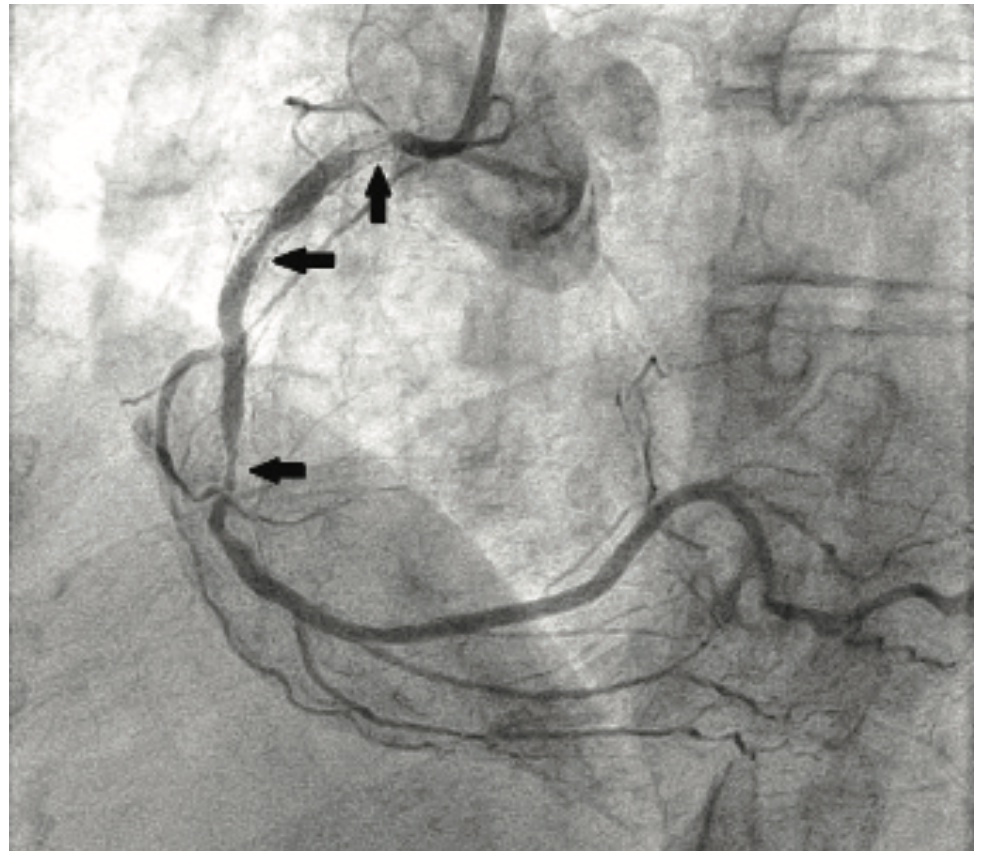

A 73-year-old woman was self-referred to our institution for coronary brachytherapy. She had symptomatic restenosis despite four prior PCI procedures entailing 5 DES over a two-year period (Figure 1). Cardiac risk factors included diabetes, hypertension, hypercholesterolemia, prior smoking, and mantle radiation for Hodgkin’s lymphoma at age 35. In June 2014, she suffered a postoperative myocardial infarction (MI) following a hysterectomy and underwent PCI of serial 90% RCA stenoses with placement of two Promus DES (Boston Scientific). In April 2015, she developed chest tightness with dyspnea and underwent a second PCI for a long 90% in-stent restenosis that was treated with a Xience DES (Abbott Vascular). In November 2015, recurrent symptoms due to a diffuse 90% in-stent restenosis led to a third PCI with placement of two Resolute DES (Medtronic). In May 2016, an abnormal stress test with inferior ischemia led to a fourth PCI procedure. Multiple 90% in-stent lesions were treated with balloon angioplasty alone. Cilostazol was prescribed, in addition to aspirin and clopidogrel. Three months later, despite optimal medical therapy, she developed unstable angina associated with new inferior T-wave inversions and inferior hypokinesis on echocardiography. She was admitted to our institution for coronary brachytherapy.

The patient’s prior procedures were performed via transfemoral approach and on one occasion, she experienced severe local pain due to vascular hemorrhage. The coronary brachytherapy procedure was performed using left radial artery access with a 6 Fr 10 cm long Slender Glidesheath (Terumo) and anticoagulation with bivalirudin. Baseline angiography showed sequential, high-grade restenotic lesions in the proximal right coronary artery (RCA) stents in addition to significant stenosis at the outflow of the most distal stent (Figure 2A). The in-stent restenosis was treated with laser atherectomy using an X-80 excimer catheter (Spectranetics) followed by balloon angioplasty with a 3.5 mm Angiosculpt scoring balloon (Spectranetics) and 4.0 mm NC Euphoria balloon (Medtronic). The most distal lesion, which extended beyond the prior stents, was treated with a new Promus DES. Coronary brachytherapy of the proximal lesions was then performed with a Beta-Cath 40 mm long source for a treatment dose of 23 Gray (Figure 2B). Final angiographic result is shown in Figure 2C. Repeat cardiac catherization at 3 months, performed because of chest pain, demonstrated widely patent stents. The patient has continued on aspirin and clopidogrel, and remains symptom-free 1 year post procedure.